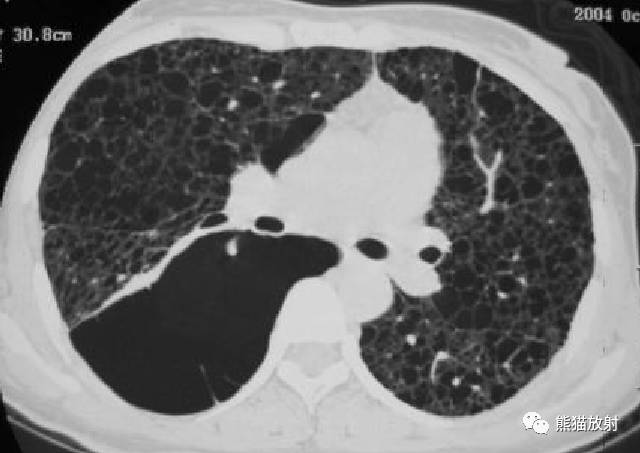

【影像表现】

胸部CT:双肺弥漫分布大小不等薄壁囊状空气密度影,且胸膜下区低密度影明显较其他部位大,周围见索条状高密度影。阴影之间肺组织基本正常。

②双肺弥漫分布囊状空气密度影,有薄壁,小叶中央动脉位于病灶边缘部分。此有别于小叶中央型肺气肿。

①小叶中央型肺气肿,见依据第二条。

②肺组织细胞增生症X(PLCH):分布以中上野为主,在显示囊状影的同时还可见多发结节。